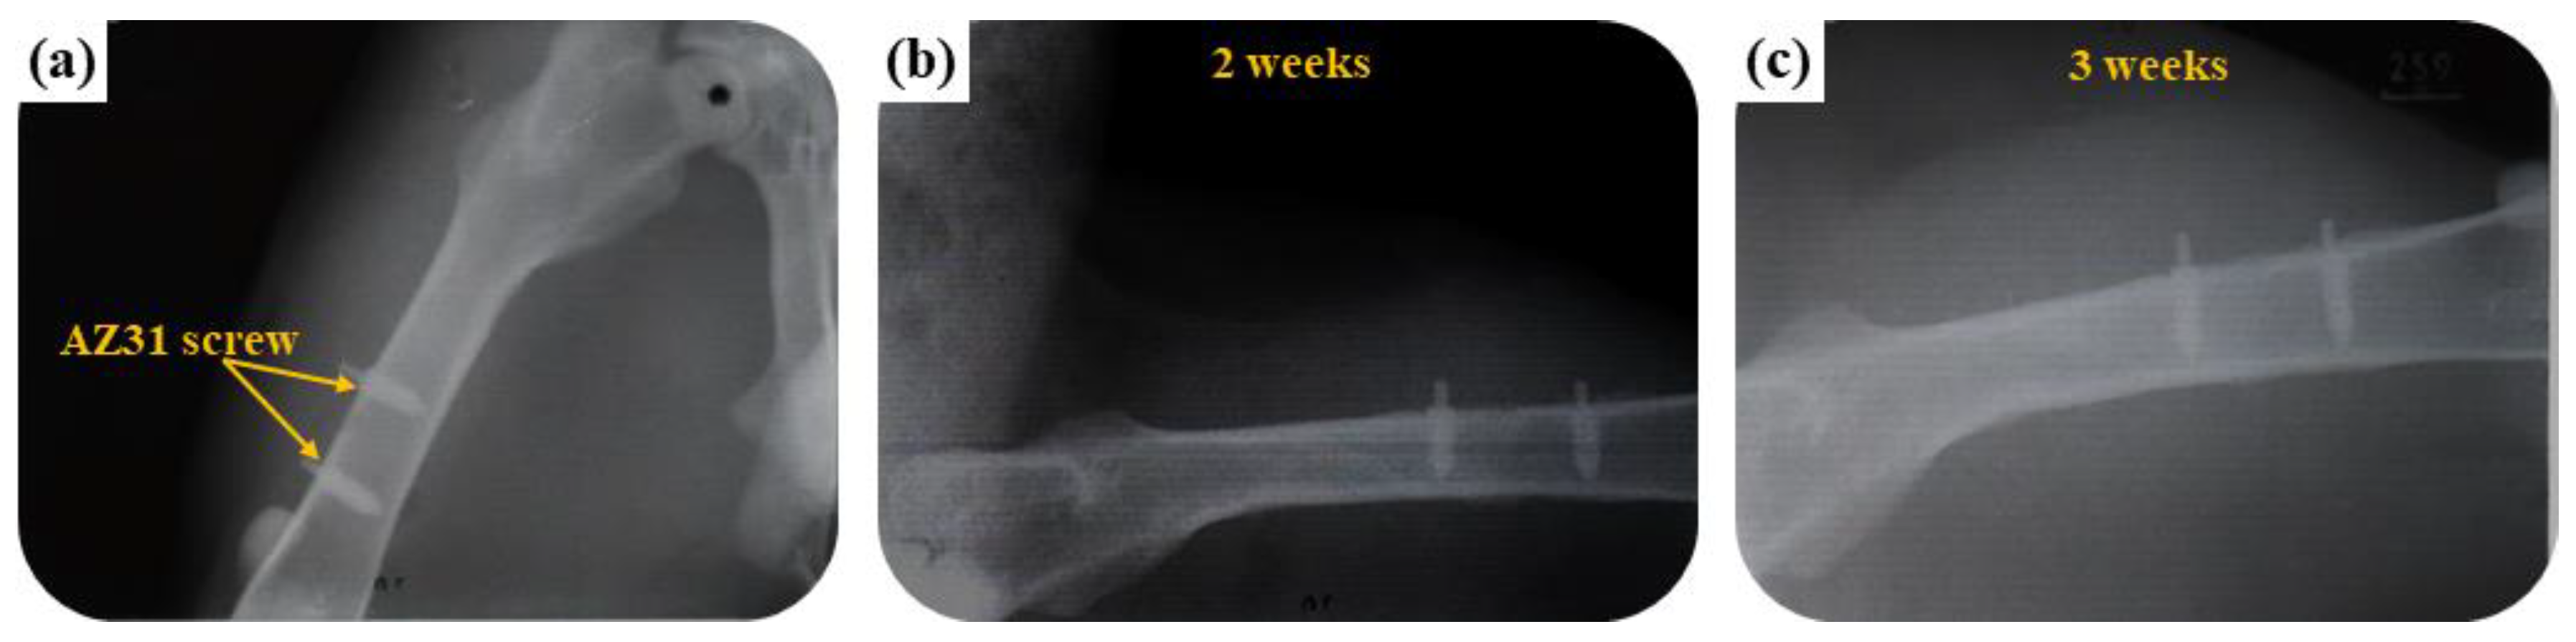

3.3.1. Radiological Examination